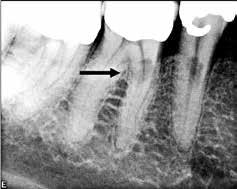

Fig. 2. Tidligere behandlet tand med insufficient eller helt manglende rodfyldning i kanalerne. A. Præmolarer i overkæben med tre insufficiente rodfyldninger og efterfølgende restaurering med stiftopbygning og krone. Desuden første molar uden synlig rodfyldning, men med restaurering, der inddrager pulpakammeret. B. Første molar i overkæben, som kun har synlig rodfyldning i den palatinale kanal. C. Insufficient rodfyldning eller overset rodkanal i første molar i overkæben.

Fig. 2. Previously treated tooth with no or inadequate root filling in canals. A. Maxillary premolars with 3 roots inadequately filled and restored with post and crown. Maxillary first molar with no visible root filling with restoration in pulp chamber and coronal restoration. B. Maxillary first molar with visible root filling only in the palatal canal. C. Inadequate root filling or missed root canal in maxillary first molar.

peroperative faktorer. En af dem er manglende behandling af en rodkanal, enten fordi den ikke blev fundet, eller fordi tandlægen ikke ledte efter den (Fig. 2A-C) (8,9). Det er påvist, at apikal parodontitis forekommer hyppigere i tænder med mindst én ubehandlet eller overset rodkanal (10). Accidentelle perforationer fører ofte til ekstraktion af tanden, men kan almindeligvis undgås med fornuftige endodontiske arbejdsgange (11). Ufuldstændig instrumentering eller forsegling af rodkanalen enten som følge af forkert rodmål eller på grund af fx instrumentfraktur, hyldedannelse eller overinstrumentering af den apikale konstriktion kan føre til, at infektionen persisterer. Rodfile kan frakturere som følge af cyklisk træthedsbrud eller vridningsbelastningsbrud, og incidensraten for brud ligger på 1 % (12). Det sted i tandsættet, der oftest giver anledning til instrumentfraktur, er den apikale del af en mesiofacial rodkanal i en molar (Fig. 3). Kraftig afbøjning af kanalen forøger risikoen for, at filen frakturerer (13). En for kort rodfyldning (> 2 mm fra radiologisk apex) har ligesom overfyldning med guttaperka en nedsat succesrate (14).